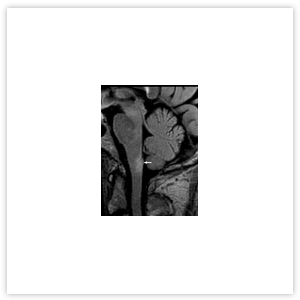

Различается и МРТ-картина заболеваний. Так, при РС в спинном мозге определяются единичные или множественные очаги, протяженностью 1–2 позвоночных сегмента, расположенные в белом веществе спинного мозга, которые обычно не распространяются на центральные отделы (Рисунок 2). При оптиконевромиелите на МРТ очаг поперечного миелита имеет, как правило, протяженность 3 и более сегмента, может распространяться на ствол головного мозга, характеризуется признаками выраженного отека, расположен в центре и заполняет более половины поперечника спинного мозга (Рисунок 3).

Рисунок 3. МРТ шейного отдела позвоночника и спинного мозга пациента с ОНМ. Центромедуллярный очаг, протяженностью 9 сегментов, сопровождающийся выраженным отеком спинного мозга